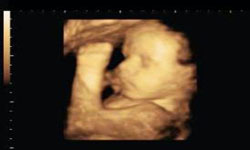

SEMANA 37 . TÚ... Quizás tengas calor a todas horas porque tu cuerpo funciona a toda máquina. Y TÚ BEBE... Su cara se redondea, tiene pestañas, su cuello se vuelve más grueso y ahora abre y cierra los párpados con facilidad.

SEMANA 38 . TÚ... Quizás tengas sentimientos ambivalentes sobre el nacimiento. Y TÚ BEBE... Su ritmo de crecimiento se vuelve más lento.

SEMANA 39 . TÚ... Tu cuello uterino se ablandará y puede que empiece a desaparecer. Puede costarte dormir debido a tu tripa. Y TÚ BEBE... Pesa unos 3kg y mide unos 50cm.

SEMANA 40 . TÚ... Quizás notes unramalazo de energía.El síndrome del nido es normal, pero descansa. Y TÚ BEBE... Sólo el 3 por ciento nace en la fecha prevista, así que si se ha pasado tu fecha tranquilízate. |